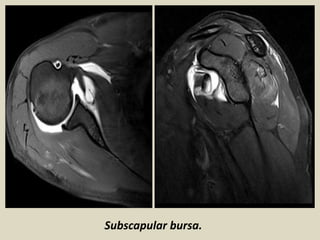

Subscapular bursa.